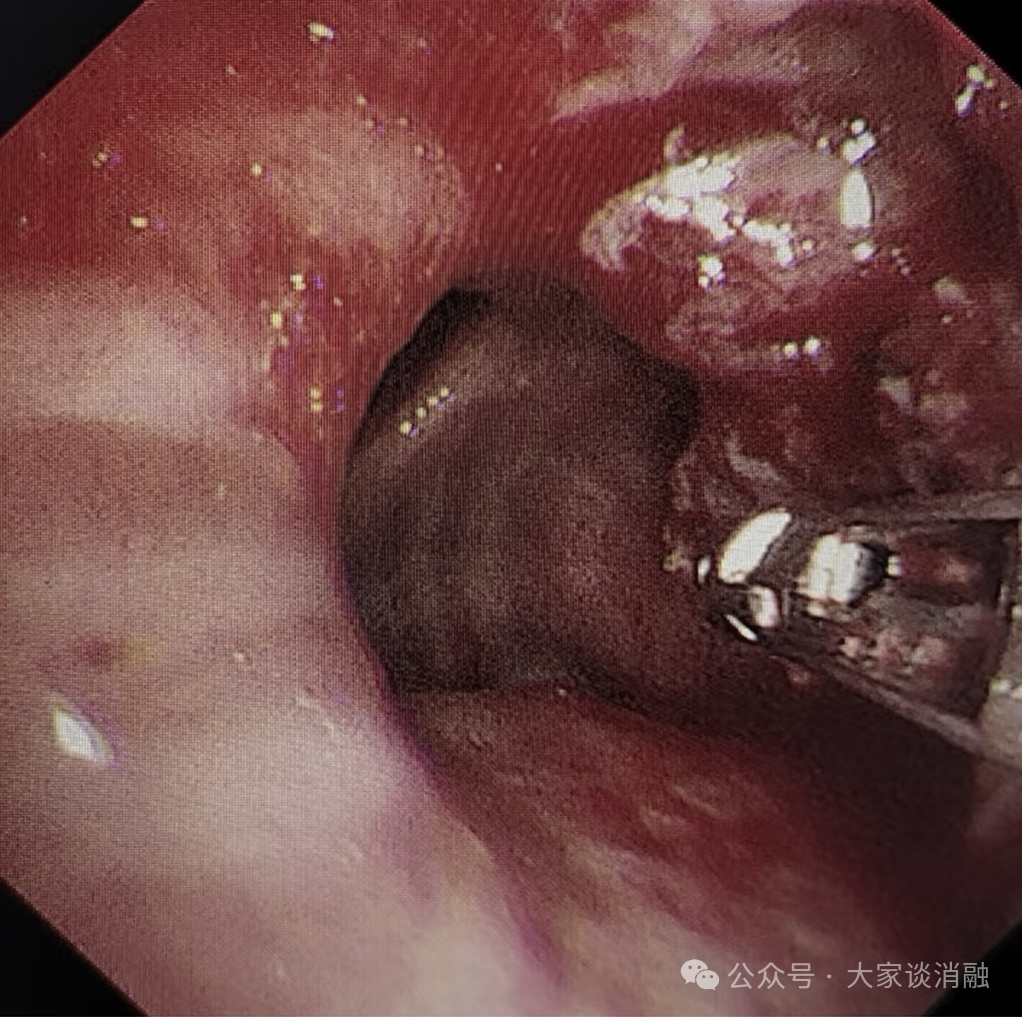

第三次治疗

10 月 29 日,为进一步巩固疗效,患者接受术后第二次镜下消瘤治疗,冷冻冻取、钳取肿瘤组织,气道阻塞问题得到更有效解决,生活质量显著提升。目前,患者已顺利出院,回归正常生活。

下叶完全开通